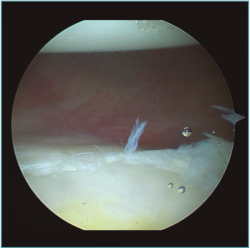

Al realizar la anamnesis, prestamos especial atención a estos síntomas ya que estos episodios repetidos de subluxaciones o microinestabilidad pueden conllevar a lesiones muy complejas e irreparables de la cápsula o, sobre todo, en el cartílago glenoideo (Figura 2).

Figura 2. Visión desde portal posterior del hombro derecho. Se observa una lesión intrasustancia de la cápsula anterior.